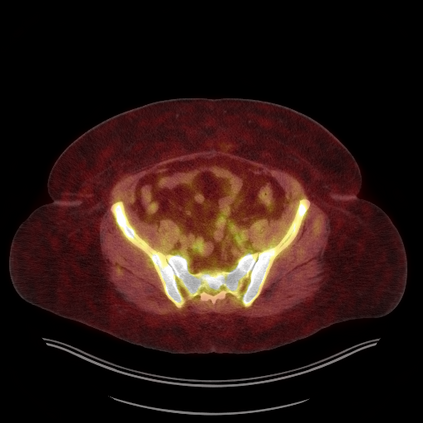

Medical images play a crucial role in assisting diagnosis, remote consultation, and academic research. However, during the transmission and sharing process, they face serious risks of copyright ownership and content tampering. Therefore, protecting medical images is of great importance. As an effective means of image copyright protection, zero-watermarking technology focuses on constructing watermarks without modifying the original carrier by extracting its stable features, which provides an ideal approach for protecting medical images. This paper aims to propose a fragile zero-watermarking model based on dual quaternion matrix decomposition, which utilizes the operational relationship between the standard part and the dual part of dual quaternions to correlate the original carrier image with the watermark image, and generates zero-watermarking information based on the characteristics of dual quaternion matrix decomposition, ultimately achieving copyright protection and content tampering detection for medical images.